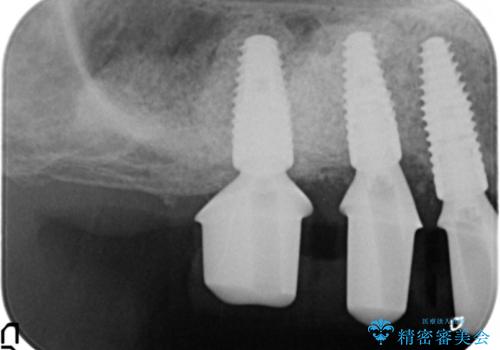

全顎的な歯周病治療を行ったのち、上顎洞底挙上術(上顎骨に骨を増やす手術)を併用したインプラント埋入を行いました。

- ¥1,400,000 (上顎洞底挙上術、GBR、インプラント×3本、アバットメント×3本、仮歯×3本、被せ物×3本)費用は治療当時の料金となります

インプラントの種類:ストローマン BLT